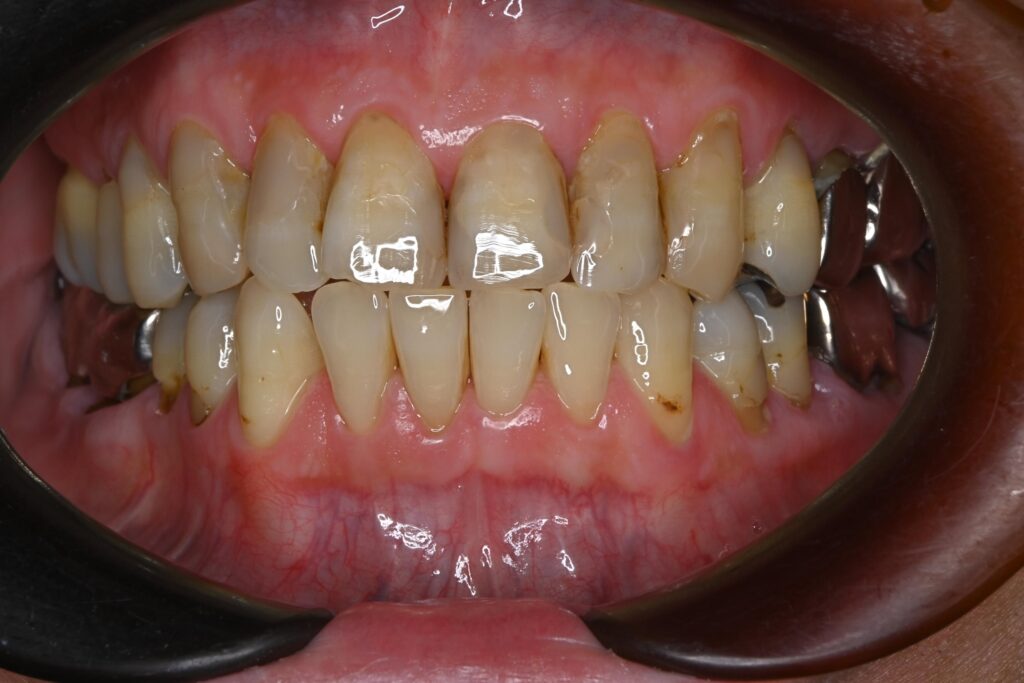

初診時の口腔内の状態:

お口全体に虫歯や歯周病の原因となるプラーク(歯垢)が多く付着していました。右上奥歯は重度の虫歯で歯冠部(歯の頭)が失われており、左下奥歯は過去の治療箇所から細菌が入り込み、根の先に炎症が起きている状態でした。

また、左右の奥歯にはWSD(楔状欠損)があり、知覚過敏も見られました。

単なる虫歯だけでなく、「切端咬合(せったんこうごう)」という噛み合わせの不調和が根本的な問題であると診断しました。この噛み合わせにより奥歯に過度な負担がかかり、知覚過敏や歯の損傷を引き起こしていました。